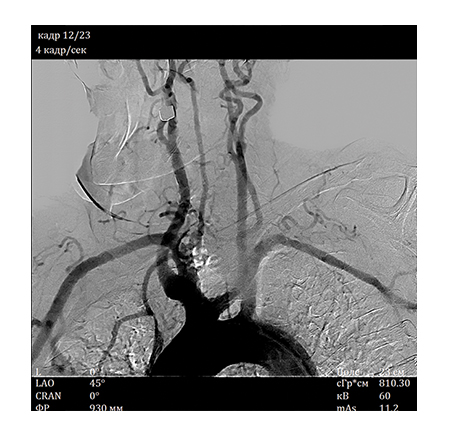

The X-ray angiography system developed by NIPK Electron Co. is a versatile system, which allows performing a wide range of diagnostic procedures:• Angiography of the brain and cervical vessels

A special value of the angiography system consists in high information content of the obtained image. A unique imaging system based on a flat panel detector with spatial resolution of 50 μm, which is superior to foreign analogs regarding its specifications, ensures high diagnostic imaging quality. The examinations allow not only to obtain information about the functional state of the vessels and reveal the signs of disorders but also help determine the accurate localization and seriousness of the revealed abnormality using special calculation packages.

• Digital subtraction angiography (DSA) with choice of subtraction level (Landmark)